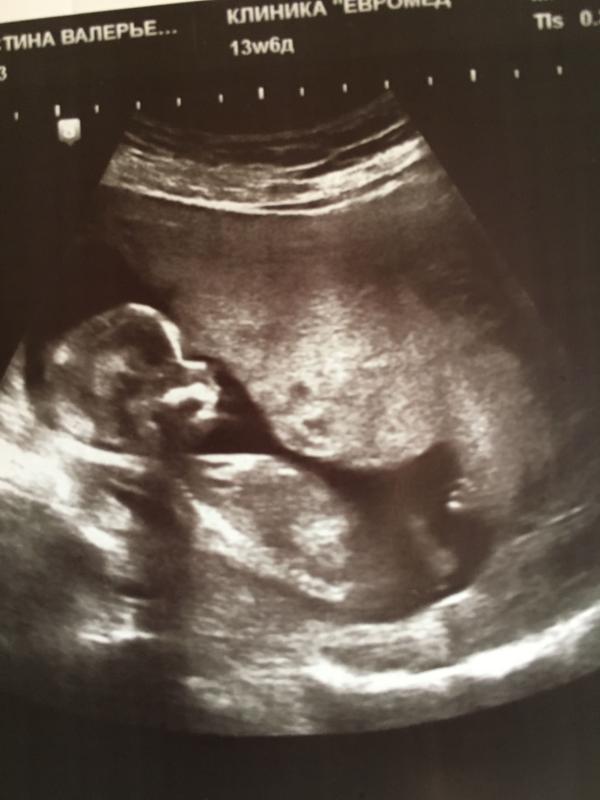

@kolomyashka, первы скрининг меея направили в 10,5 недель а на у узи сказали что 12,4 даже пол ребенка сказали

@kolomyashka, спасибо 😊 да с первого узи мне и ставят на две недели в перед. А первое узи у меня было в в 4 недели по м. А поставили 6 недель.